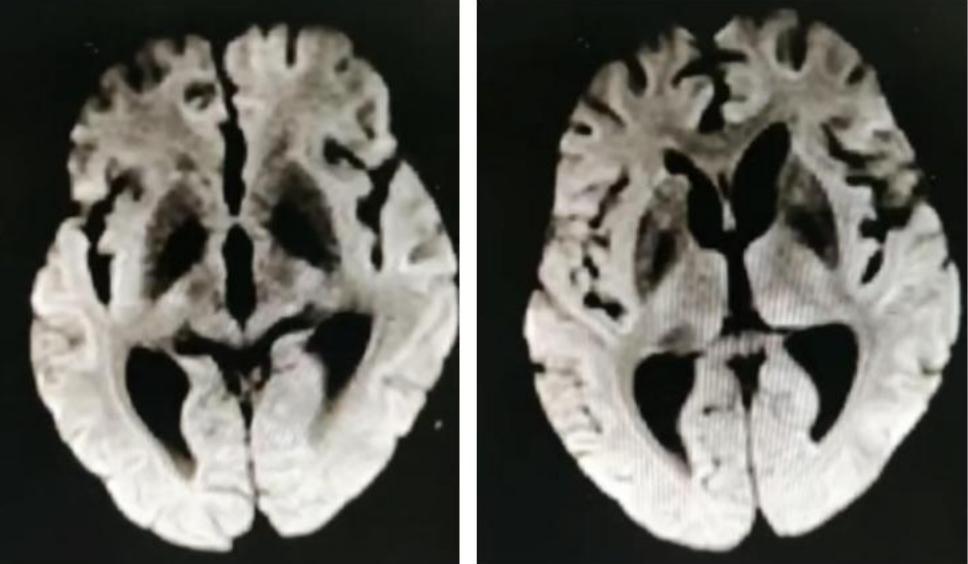

男性68岁,四肢末梢麻木2月余,伴有站立不稳,加重1周,不能独立行走。查体双侧跟膝胫试验欠稳准,双侧位置觉、震动觉减退。

答案:脊髓亚急性联合变性。患者老年男性,亚急性病程,以深感觉受累为主要表现,脊髓影像长节段病灶,轴位显示后索病灶“圆点征”,颅内影像改变无特异性,NMOSD相关抗体检测以及OB均阴性。其特征性影像有“圆点征”、“小字征”、“三角征”、“八字征”等。